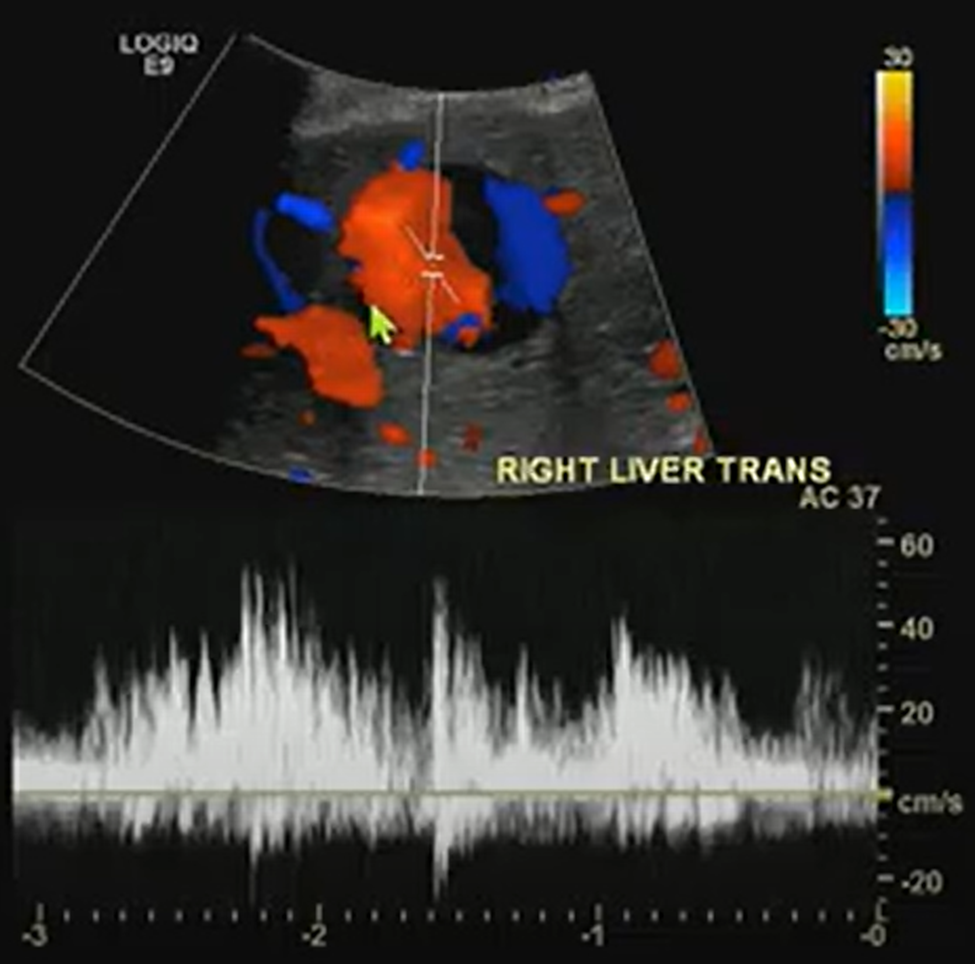

A benign-looking liver lesion turned out to be a hepatic artery pseudoaneurysm—all thanks to color Doppler.

What looks like a simple hypoechoic cyst on ultrasound may hide a critical vascular pathology. Color Doppler is essential for distinguishing cystic lesions from vascular anomalies like pseudoaneurysms.

- The Pepsi Sign: Swirling vascular flow within a lesion may signal a pseudoaneurysm.

Never skip Doppler. The “Pepsi sign” may be the clue that transforms a benign-looking lesion into a critical vascular diagnosis.